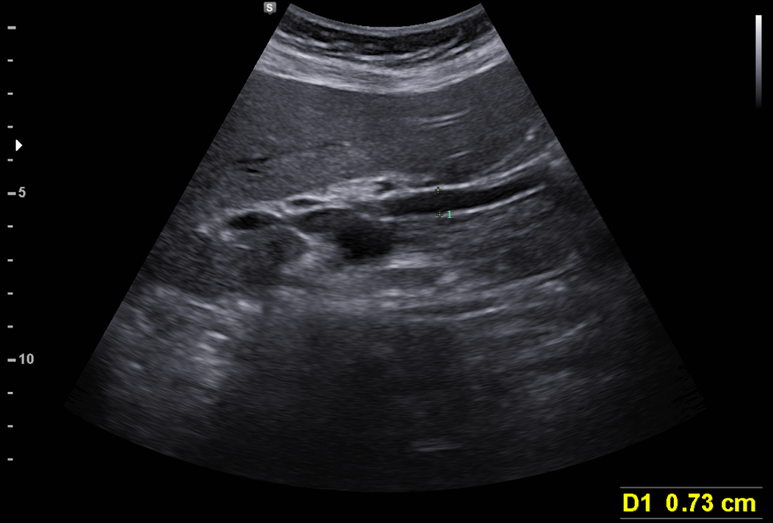

나이에 비해 총담관이 늘어나 있다. 총담관의 폐색? 임신에 의한 담도 확장?